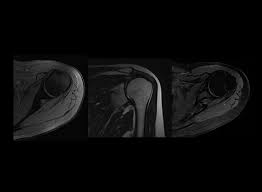

An upright mri allows patients to be scanned while standing or sitting, which can be helpful in diagnosing certain conditions. Does it seem you have no choice in where you go and what you pay for a radiology procedure? Private physios, paying for mri scans & torn shoulder problems. Estimate the cost of your mri or ct scan at american health imaging with our simple calculator. However, there are also alternatives such as ultrasound, which can also confirm rotator cuff tears.

Sale de inverno shoulder com até 70% off. If a person receives an mri scan at the. But blue cross pays about half that amount: Check with your insurance provider and be tough sometimes they don't give out the info readily. However, the average shoulder mri costs around $1500. How much does a mri/ct with arthrogram cost? An upright mri allows patients to be scanned while standing or sitting, which can be helpful in diagnosing certain conditions. The national average cost for an mri at inpatient facilities is $2,250, while the same procedure at outpatient facilities averaged $650.

Estimate the cost of your mri or ct scan at american health imaging with our simple calculator. Please contact your physician's office and health insurance provider directly for price information. How much does an mri cost? If patients have not hit their deductible, that money comes straight. Surgeries / operations (head & torso) The cost of an mri will vary greatly between inpatientand outpatient facilities. How much does an mri cost? Those on high deductible health plans or without insurance can save when they buy their procedure upfront through mdsave. Although they may not say so, some physicians in health care systems or hospital groups are contracted with hospitals. If a person receives an mri scan at the. Our experienced staff are friendly and approachable, and can answer any. A shoulder mri is done to check a shoulder for arthritis, bone tumors, torn ligaments or tendons, and other similar problems. Read more about how mdsave works.